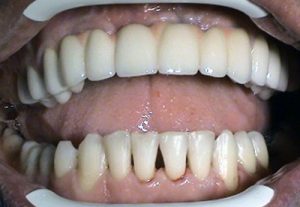

1. PHASE – implant insertion

2. PHASE – state before making immediate impressions